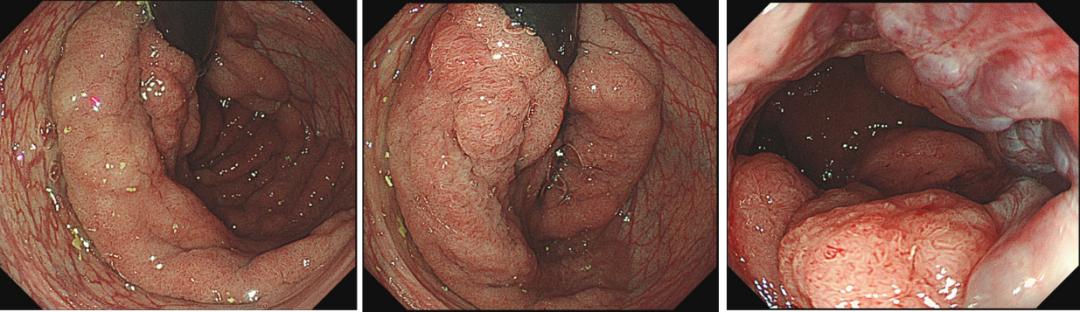

肠镜检查:直肠距肛门15cm以下发现环周大肠侧向发育型肿瘤(LST)病变,该病变累及齿状线,表面分型为结节混合型。

图1为了进一步了解病变的性质和深度,对患者进行了放大内镜的观察,发现病变的毛细血管形态和表面微结构包括:CP II+IIIA型,Pit IIIL、IVb、IVv、Vi型,JNET 2A+2B,提示病变的局部可能发生了癌变。